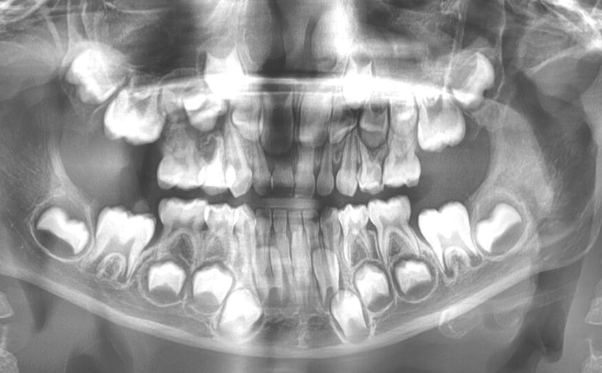

Dental X-rays are essential diagnostic tools that reveal hidden problems invisible to the naked eye. Our advanced digital imaging provides detailed views of your teeth, roots, and jaw bone with minimal radiation exposure, helping us detect issues early and plan precise treatments.

Our advanced digital X-ray system delivers instant, high-resolution images with up to 90% less radiation than traditional film — about the same as a short flight. It’s fast, accurate, and comfortable. Your dentist will review your symptoms and goals to choose the right type of X-ray — bitewing, periapical, panoramic, or CBCT. You may need to remove metal accessories, and a lightweight apron or collar adds extra protection. The process is quick: small sensors are placed briefly in your mouth, or a panoramic/CBCT scan takes less than a minute. Results appear instantly, and your dentist will walk you through the images, point out any concerns, and explain the next steps clearly.

Dental X-rays play a key role in comprehensive care at every age, helping reveal issues that aren’t always visible during a routine exam. They’re used to establish a baseline for new patients, investigate symptoms like pain or swelling, and support treatment planning for fillings, orthodontics, implants, and more. With safe, targeted imaging tailored to each person’s needs, both children and adults benefit from early detection, accurate diagnosis, and more effective care.